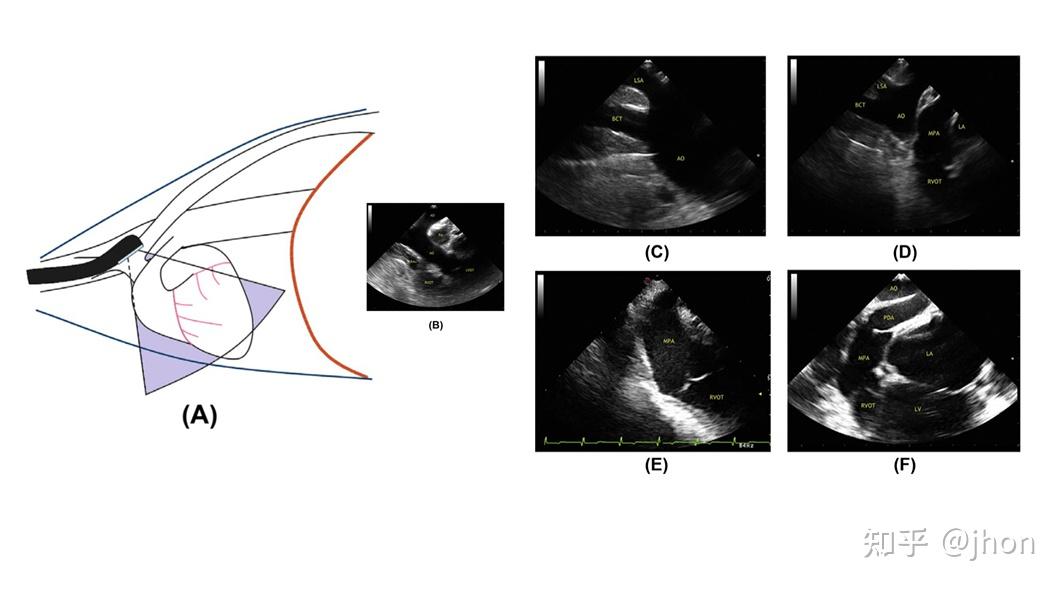

犬经食道超声心动图tee切面获取攻略